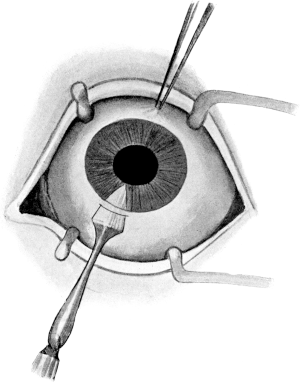

| 85. | Eye Speculum | 191 |

| 130. | Tenotomy | 249 |

| 131. | Tenotomy by the Open Method | 250 |